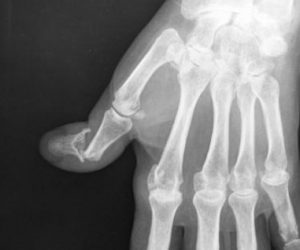

A destruição articular geralmente provoca luxação ou sub-luxação da articulação com erosão da base de F2 e afunilamento da extremidade distal de F1.

O tratamento está limitado à fixação cirúrgica da articulação (Artrodese). Estas artrodese podem ser feitas de várias formas.

Figuras 30 e 31: Luxação IF; artrodese articular